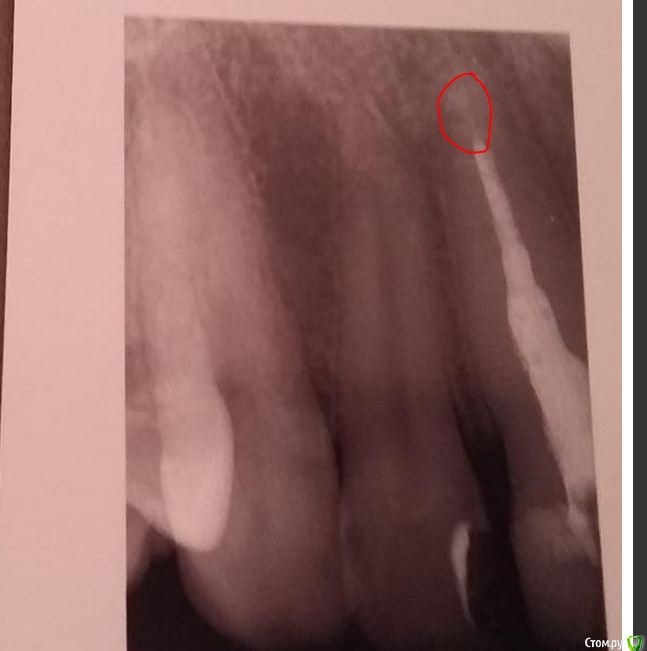

St. Опубликовано 18 августа, 2015 Поделиться Опубликовано 18 августа, 2015 (изменено) Снимок совсем размытый получился. Попробуйте перефотографировать. Скорее всего они говорят об этом участке Изменено 18 августа, 2015 пользователем St. 1 Ссылка на комментарий

St. Опубликовано 18 августа, 2015 Поделиться Опубликовано 18 августа, 2015 (изменено) там вроде видна слабая тень материала. Мне кажется, не стоит пока трогать этот зуб. Просто через 6 и 12 мес повторить прицельные снимки. 100% при лечении каналов не бывает в принципе, может быть например 99.. потому что прогноз зависит не только от доктора , а в том числе и от вашего организма, на который мы не всегда можем повлиять. Изменено 18 августа, 2015 пользователем St. 1 Ссылка на комментарий